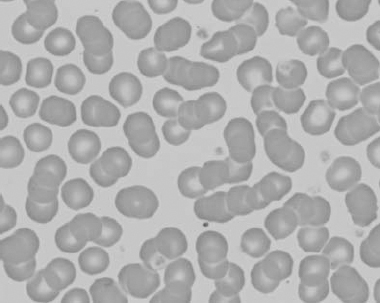

Figure 1.23 Canine blood film showing rouleaux formation (also see color section).

Figure 1.24 Canine blood film showing spherocytosis and polychromasia due to immune-mediated hemolytic anemia (also see color section).